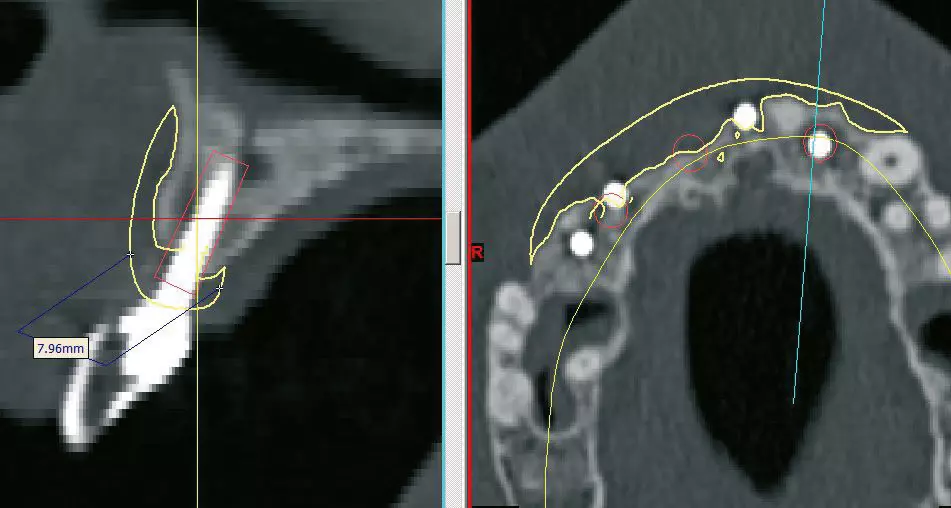

- Juli 2018: Transplantation eines durch digitalisierte Planung individuell an die Defektregion des Patienten angepassten allogenen Knochenblocks (Abb. 15).

- Januar 2019: Insertion von definitiven Implantaten im allogenen Knochenblocktransplantat regio 015, 013,021,022 sowie direkter Sinuslift regio 026 und 027.

Operationsprotokoll II – Januar 2019

Nach sechsmonatiger Einheilzeit des Augmentats (Abb. 22 und 23) erfolgte im Januar 2019 das Re-Entry (Abb. 24). Die Mikrofixturen/Osteosyntheseschrauben wurden entfernt und vier definitive Implantate (T3, Zimmer Biomet Dental) mit einem Drehmoment von 30 Ncm nach vorherigem Gewindeschneiden (Abb. 25) inseriert: regio 015 (4,0 mm x 13 mm; simultaner direkter Sinuslift), 013 (4,0 mm x 13 mm), 021 (4,0 mm x 13 mm), 022 (3,25 mm x 13 mm). Der Knochenblock zeigte eine gute Osseointegration und Vaskularisierung, lediglich in regio 012 war er leicht gelockert, jedoch periostal gestielt (Abb. 26).